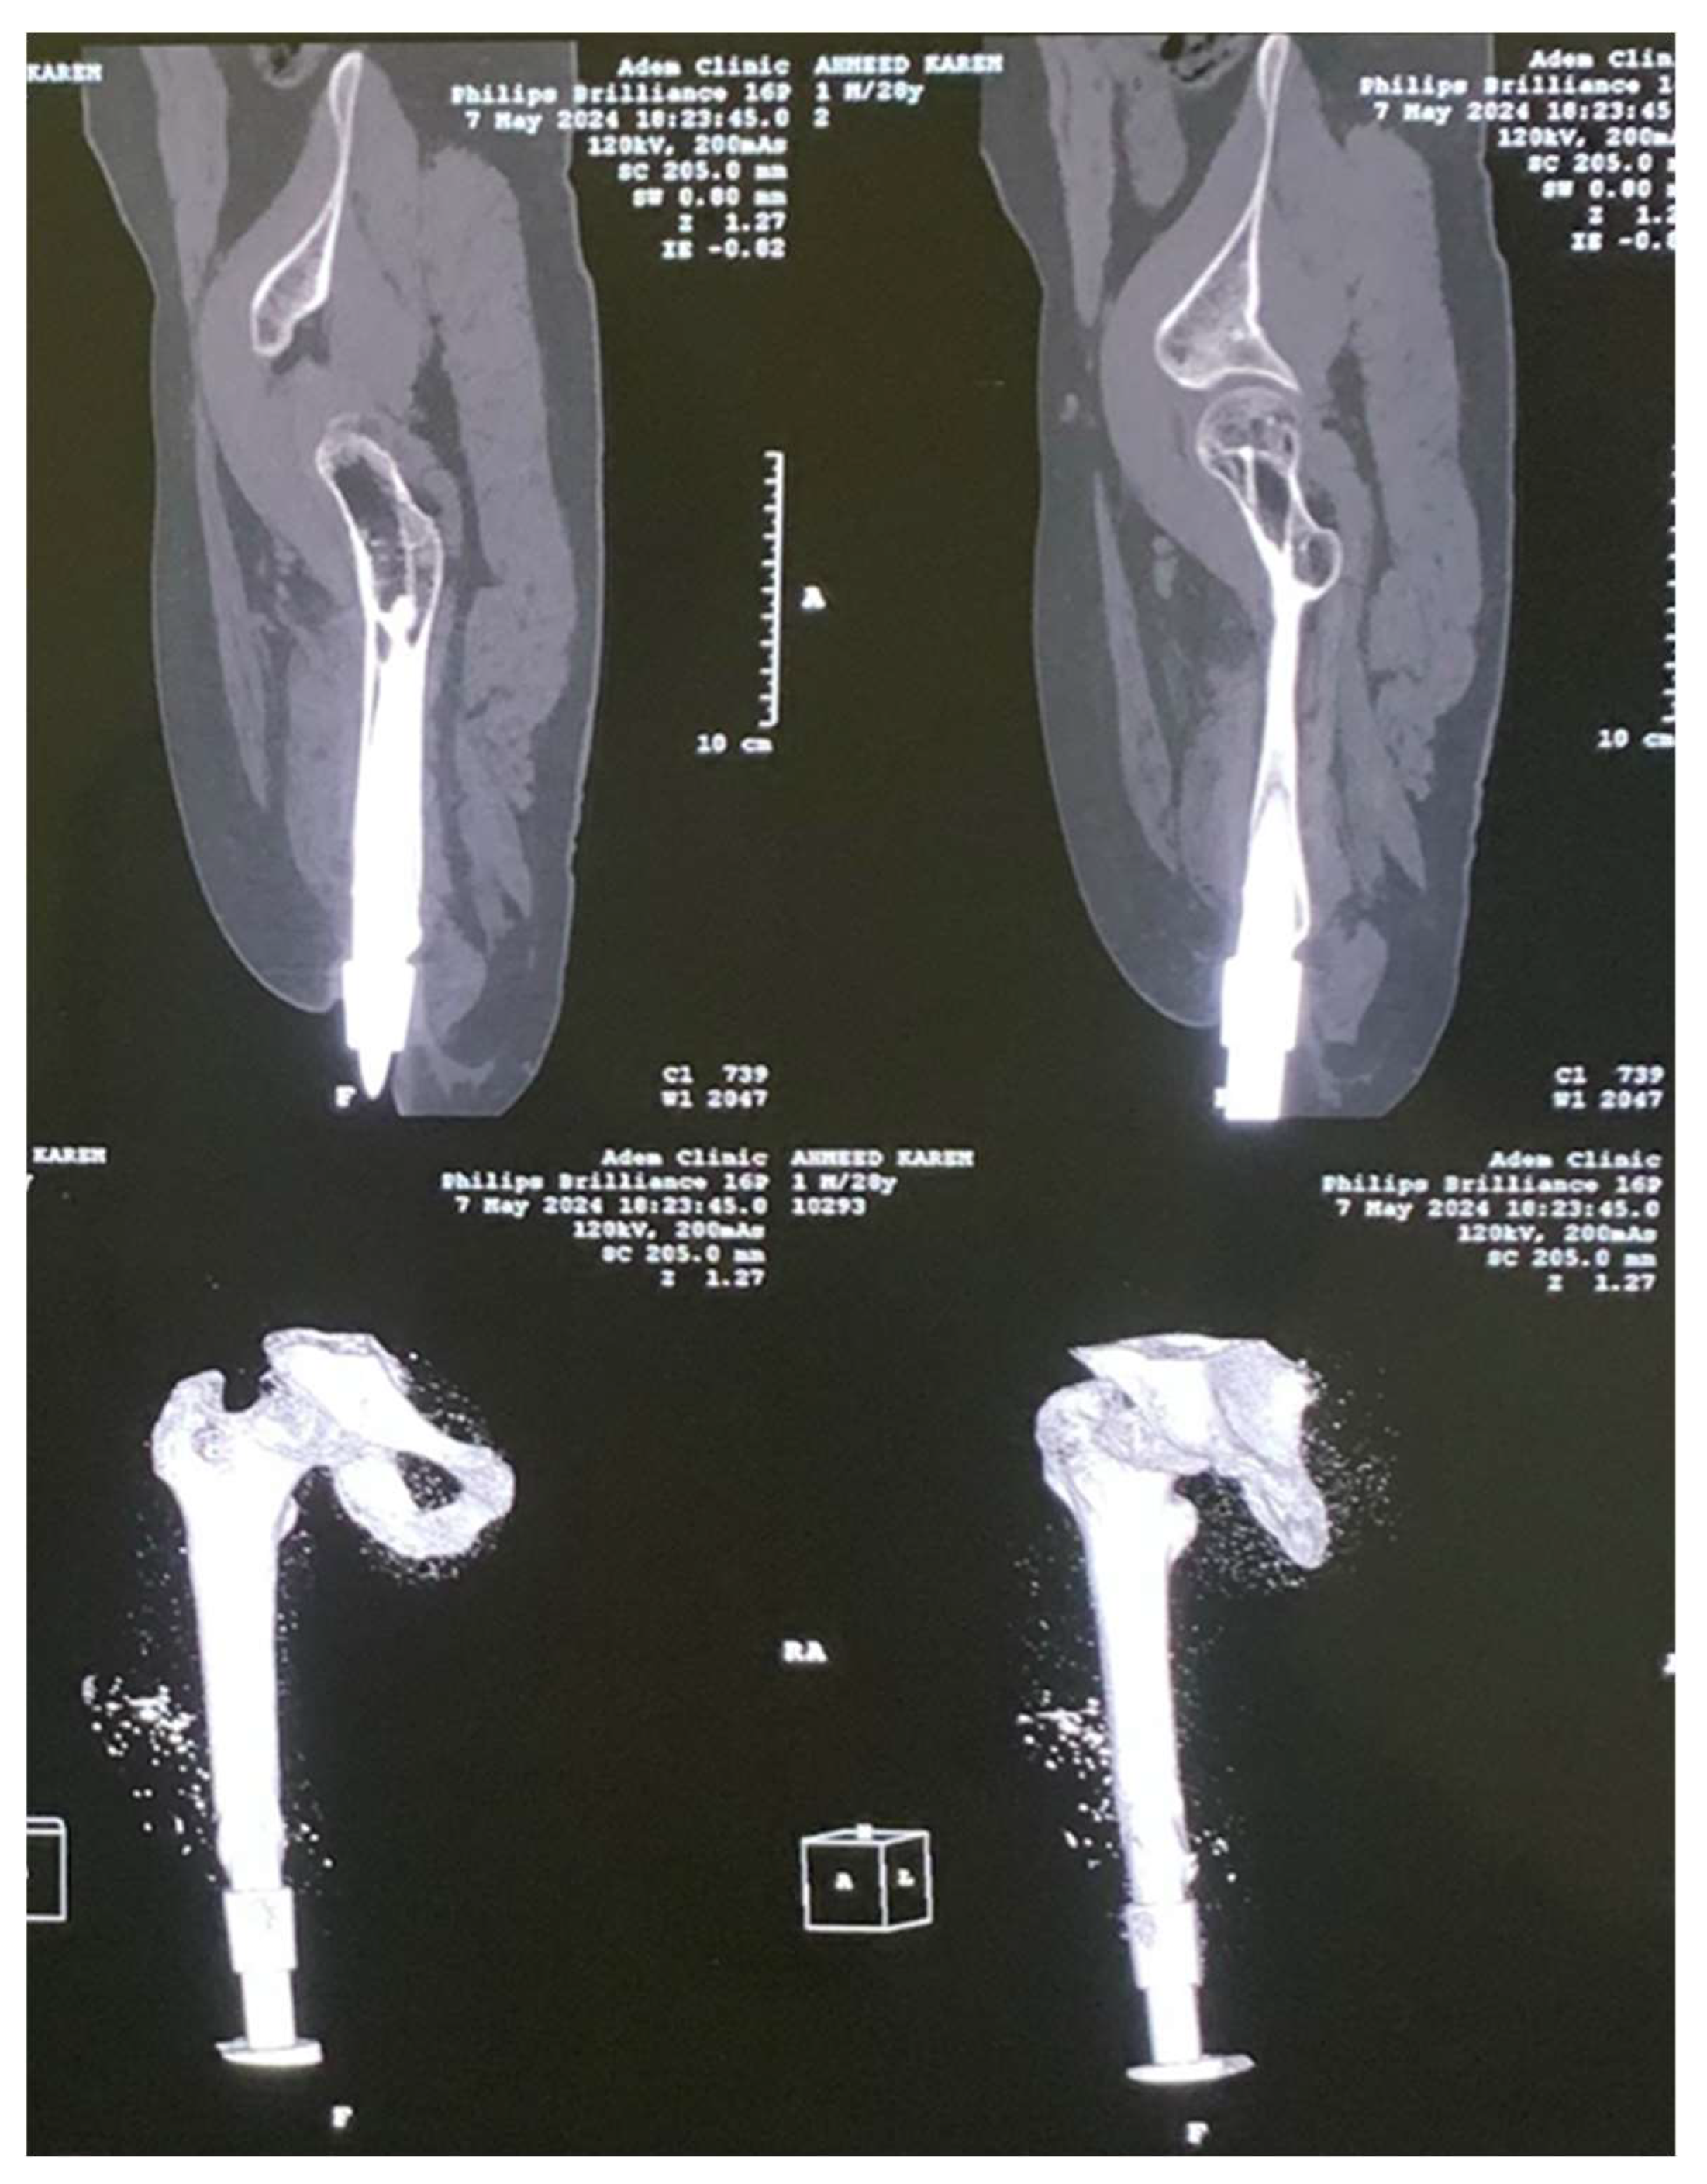

2. Experimental Works

3.1. CAD Model